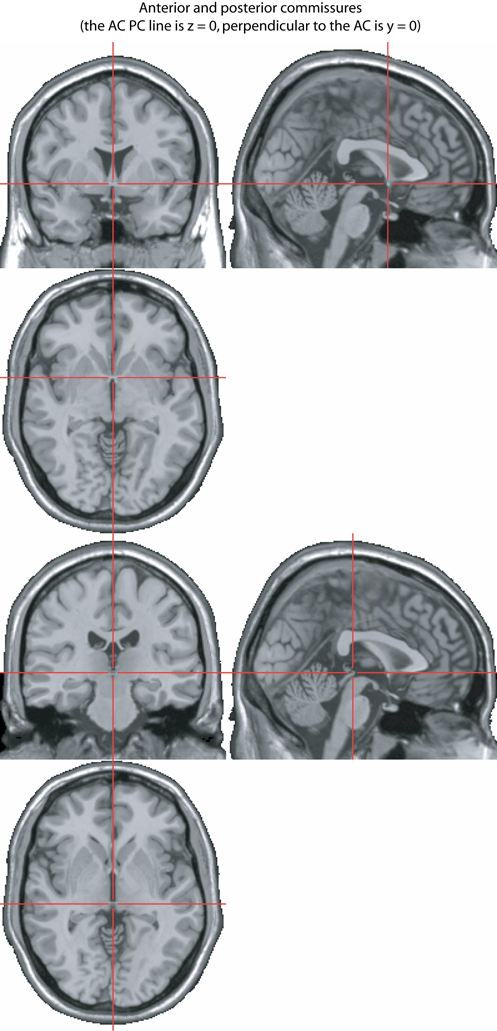

This is explained in detail on this page of Chris Rorden. See also the figure below, which was taken from the MRC CBSU Wiki.